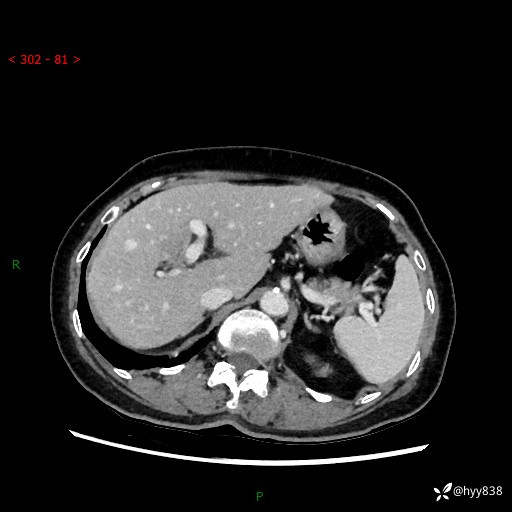

上腹部CT平扫+增强